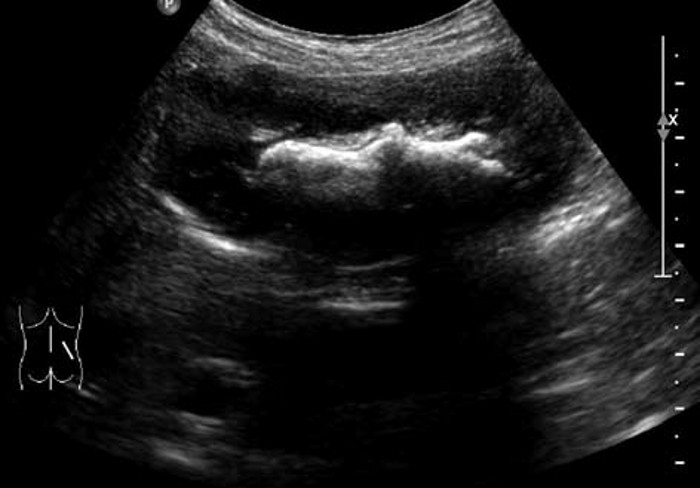

肾结石的超声图像,肾结石超声诊断及鉴别 2. 中等结石:高强团状回声一般呈新月状,后方声影明显。尿酸、胱氨酸、黄嘌呤结石较疏松,隐约可见光团全貌,后方声影浅淡。

3. 鹿角状结石:大而分叉,形态不规则,超声往往仅显示局部突起的表面,呈几个孤立的强光团或弧形强回声带,像多个结石,但连续扫查可出现互相连续的一体。

患者,男,12岁,因运动后多次突发腹痛,腹痛不能缓解并伴有恶心,面色苍白来院就诊,尿常规检查可见红细胞。超声检查显示:双肾大小形态大致正常,轮廓清,包膜光滑,实质回声尚均,呈低回声。右肾未见明显分离,左肾集合系统分离约1.1cm,左肾内可见0.9cm×0.7cm强回声,后方有声影。

超声提示:左肾集合系统分离,左肾结石。